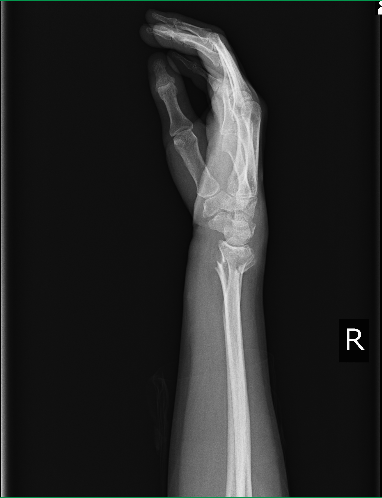

〇橈骨遠位端骨折

整形外科でトータルで8週近く固定をされました。リハビリを希望し週一回受けることができましたが、毎回いきなり動かす運動療法は強い痛みを伴いました。

経過が良くないことを医師に伝えると本人の努力が足りないと逆に怒られてしまいインターネットで当院を探し相談に来院されました。

当初は手はパンパンに腫れ、安静にしていても痛みがひどく寝ることもできない状態でした。

指の先まで浮腫があり指関節 手首の動きが制限される関節拘縮です。

軽度のマッサージと超音波治療から根気よく継続することにより症状は徐々に緩和し関節拘縮も消失して全く生活に支障のない状態までに回復しました。